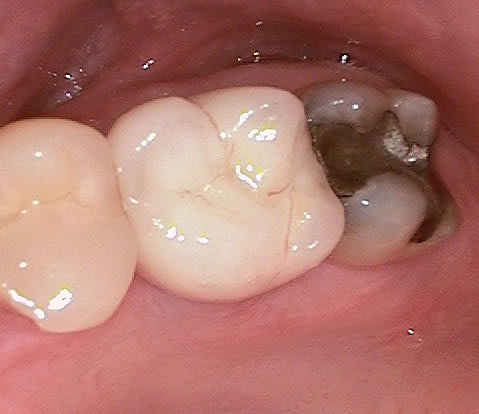

J'ai regardé toutes ces réhabilitations. Le truc qui me chiffonne dans tout ça (sur lequel je m'interroge, pour parler en français académique), c'est la façon dont on assure l'hygiène, avec des embrasures aussi petites et des prothèses qui semble bien proches de la gencive.

En bref : comment ça se nettoie ?

c est une bonne question (merci de m avoir expliquer le sens de chiffonne :-) l expression est marrante)

une bonne hygiène est surtout importante si le patient est malade par exemple suite à un "schlaganfall" (en allemand je ne sais pas le terme en francais)

les "vieux" systèmes deux pièces ont un micro espace de 30 micromètres , ce qui explique que les patients devaient nettoyer péniblement ...

en ceramique il n y a pas d accumulation de plaque donc pas de grandes concentration de bactéries gram negatif et anaerobie.La gencive se forme très bien autour de la ceramique ( la nature est le meilleur architecte!)

si après quelques années les couronnes sont retirées, on voit pas d infection....

pour finir c est sur qu il faut quand même se brosser les dents régulièrement. Les patients reviennent juste deux fois par an pour un nettoyage professionnel...

Oui tu as bien raison :-) Ci joint quelques photos en rapport avec ta question ....